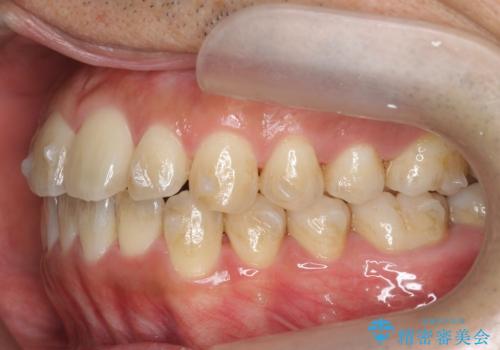

- 前歯のガタつきをきれいにしたい、と矯正治療を希望され来院されました。

マウスピース矯正インビザラインを用いてガタつきをきれいに並べていきます。

外側に傾斜していた前歯の角度も良くなり、「前歯の見た目が良くなった。」、と喜んでいただくことができました。